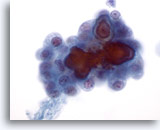

Positief voor maligniteit

Bij de monsters in deze categorie geldat dat bij resectie in bijna 100% van de gevallen een maligniteit wordt gevonden. Papillair carcinoom is de meest voorkomende maligniteit van de schildklier en heeft specifieke nucleaire kenmerken die eenvoudig zijn vast te stellen bij cytologische monsters. Andere maligniteiten waarvan de diagnose zeer nauwkeurig kan worden vastgesteld op basis van cytologie, zijn onder andere medullaire carcinomen, lymfomen, en metastatische carcinomen. Papillair carcinoom wordt gekenmerkt op ThinPrep door lagen en papillaire clusters van opeengepakte cellen met kernvergroting en molding, poederige chromatine, onregelmatige kerncelmembranen (met name kerngroeven en intranucleaire cytoplasmische inclusies), en kleine maar prominente en vaak eosinofiele nucleoli.[7] Daarentegen wordt medullair carcinoom gekenmerkt door geïsoleerde monomorfe plasmacytoïde cellen, die een hoge kern/cytoplasma-ratio hebben, excentrische kernen en grofkorrelige chromatine met of zonder een prominente nucleolus. Kleine, onopvallende granulen vullen het cytoplasma. Soms lijken de cellen spoelvormig, maar vertonen ze dezelfde nucleaire kenmerken. Lymfomen en metastatische carcinomen van de schildklier komen veel minder vaak voor. Hun cytologische kenmerken hangen af van het type en de plaats van oorsprong.